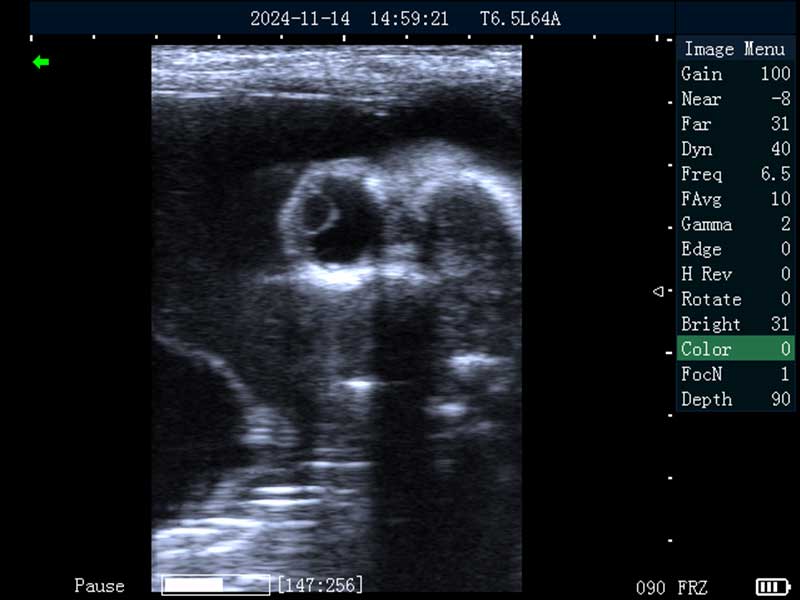

牛妊娠65日龄